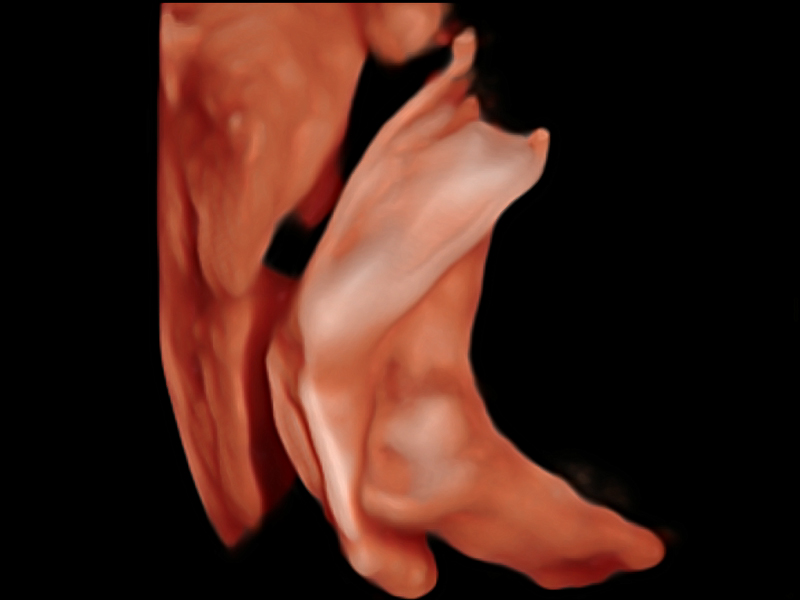

新一代微米成像技術(shù)大大提高了器官和病變的可見性。高清對(duì)比度分辨率將抑制斑點(diǎn)噪聲,同時(shí)保持真實(shí)的組織結(jié)構(gòu)。